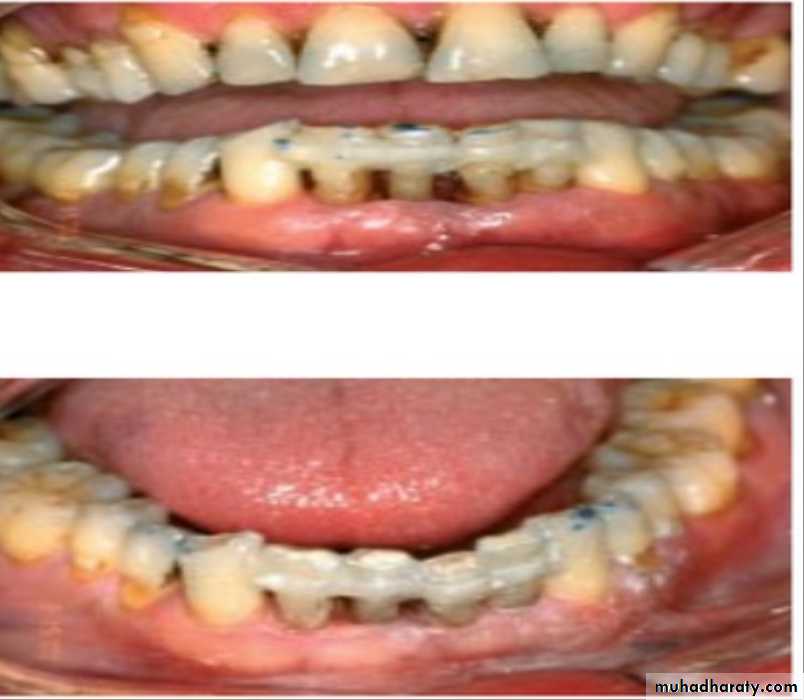

6)Temporary, provisional or long-term stabilization of mobile teeth with removable or fixed appliances.

7)bite plane,night guard,now called [inter-occlusal appliance] a-prevent teeth from fully interdigitating. b-help in preventing or minimizing isomeric contraction of muscles